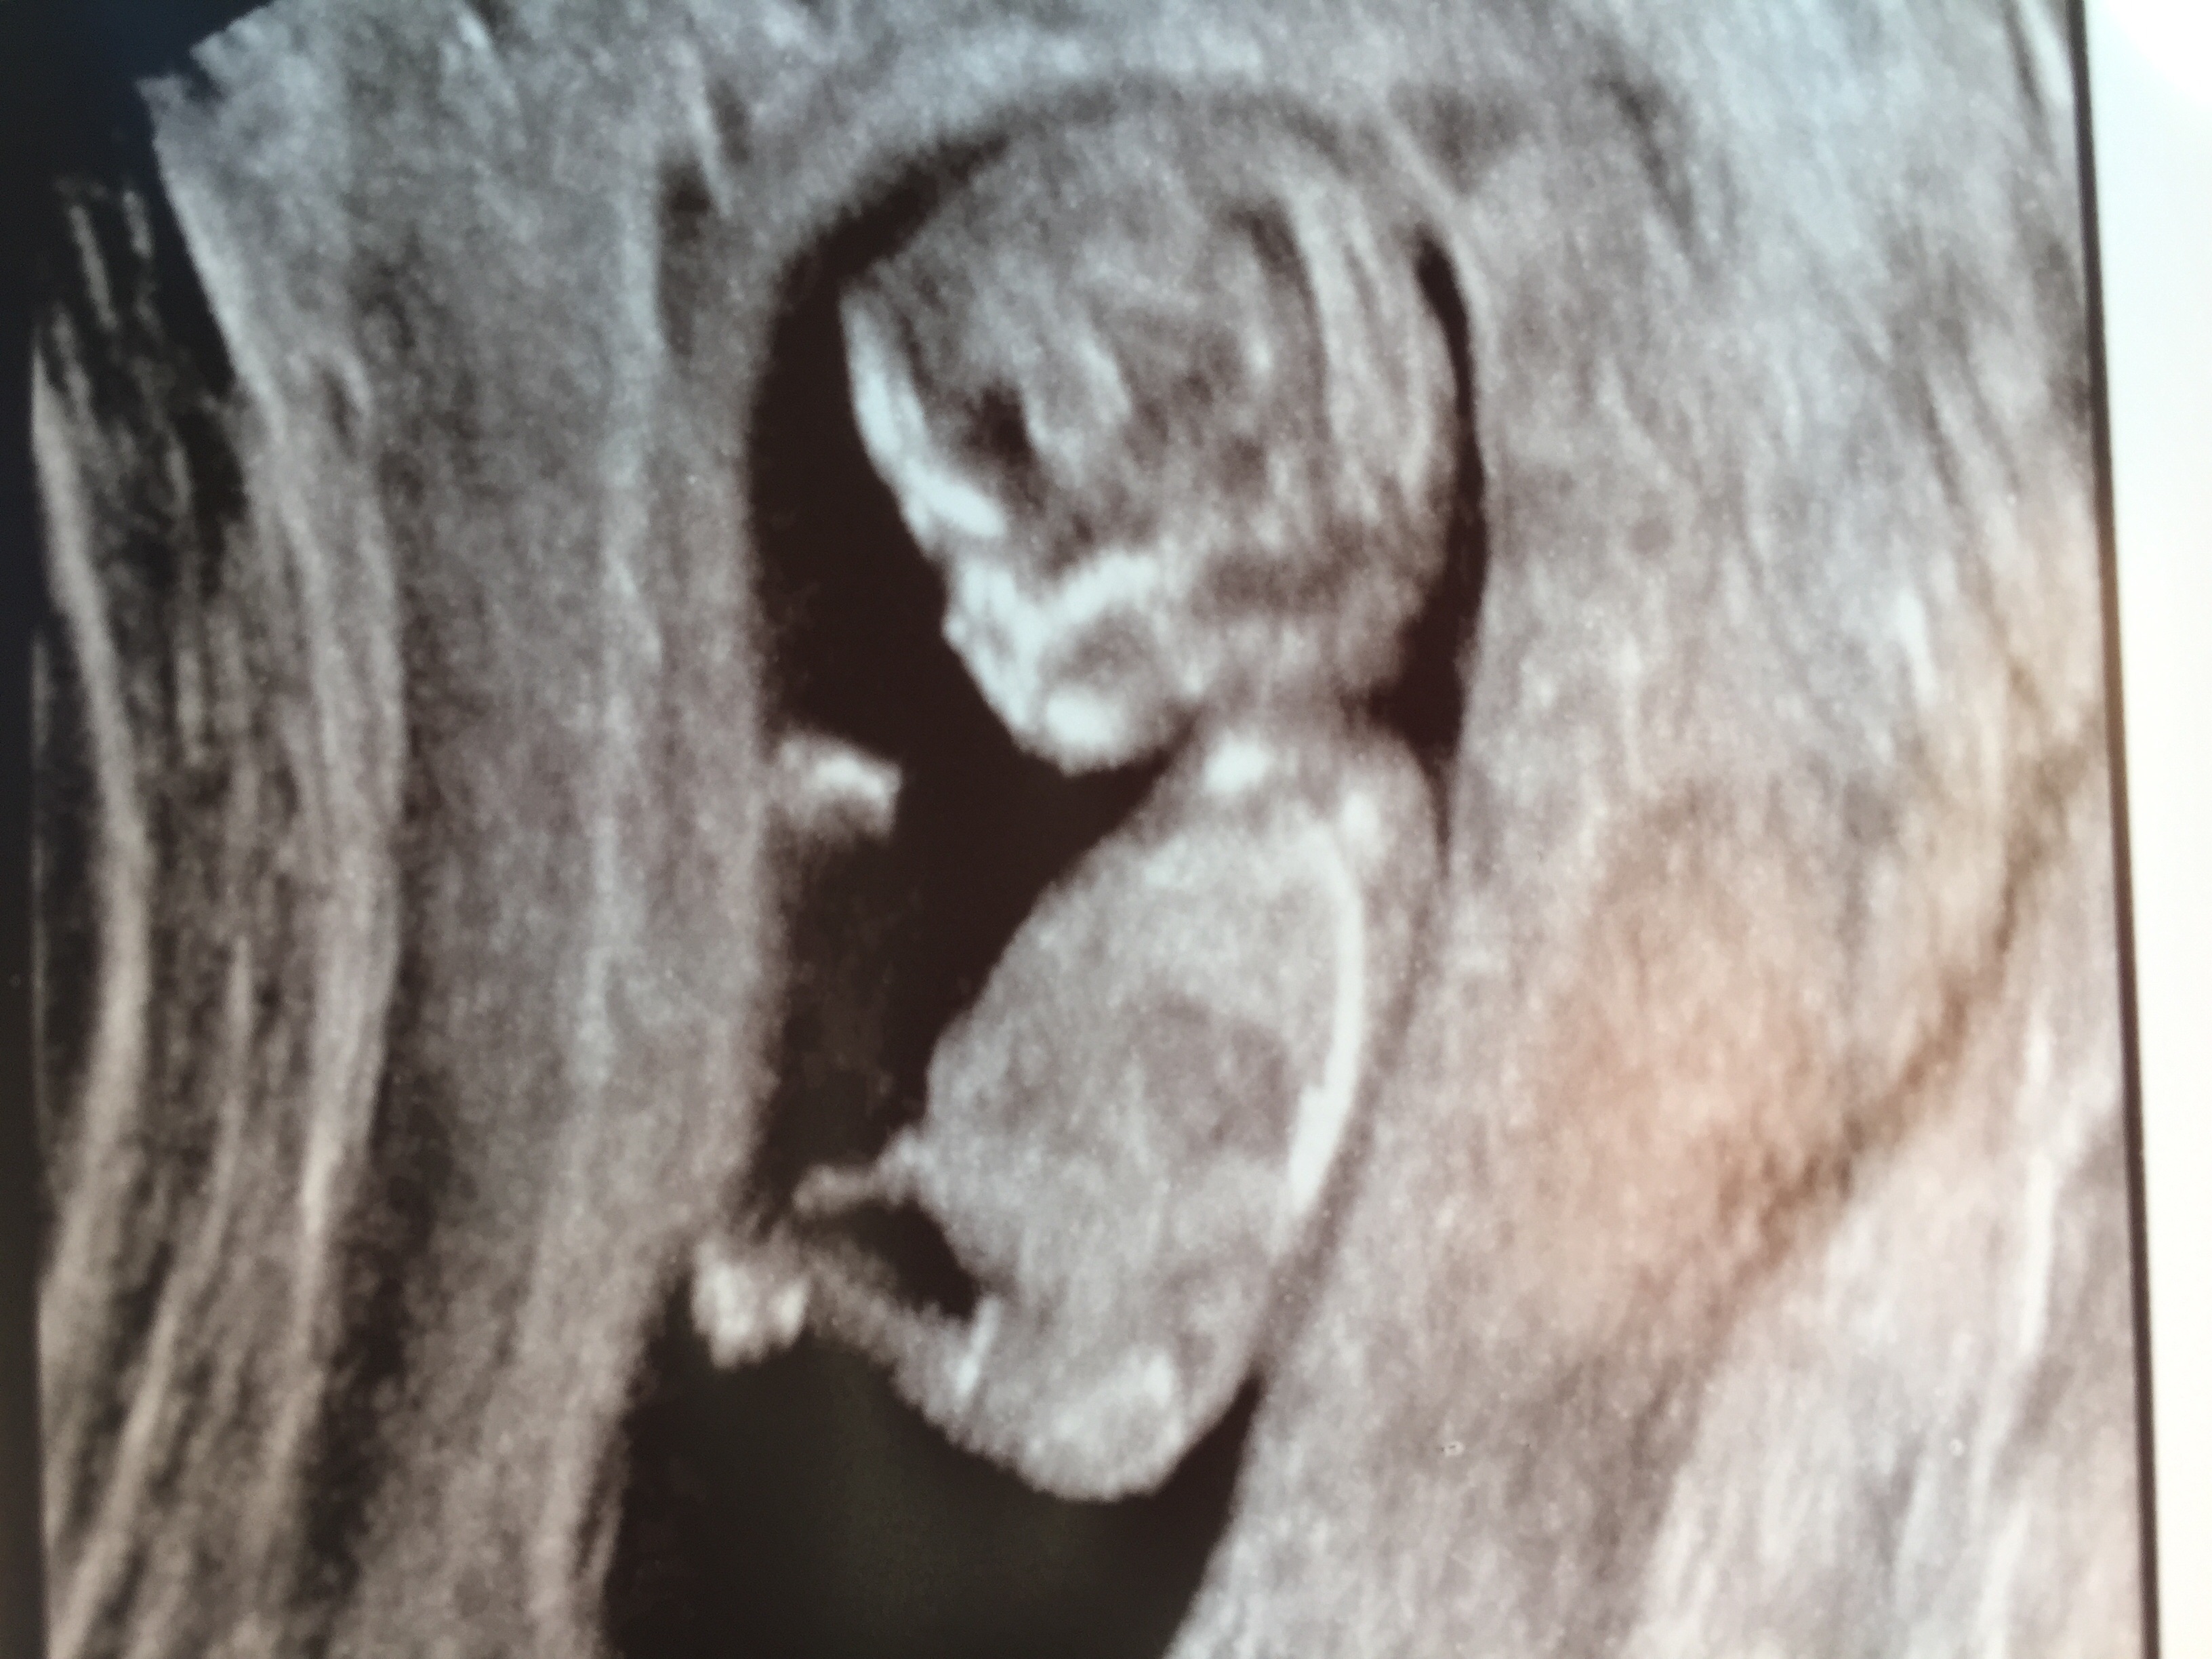

12 weeks 2 days, what do you think?!